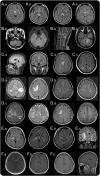

Figure 1. MRI lesions characteristic of neuromyelitis optica spectrum disorder

Diencephalic lesions surrounding (A.a) the third ventricles and cerebral aqueduct, (A.b) which include thalamus, hypothalamus, and (A.c) anterior border of the midbrain. (B.a) Dorsal brainstem lesion adjacent to the fourth ventricle, (B.b) linear medullary lesion that is contiguous with cervical cord lesion, (B.c) edematous and extensive dorsal brainstem lesion involving the cerebellar peduncle. (C.a) Callosal lesion immediately next to the lateral ventricle, following the ependymal lining, (C.b) “marbled pattern” callosal lesion, (C.c) “arch bridge pattern” callosal lesion. (D.a) Tumefactive hemispheric white matter lesions, (D.b) a long spindle-like or radial-shape lesion following white matter tracts, (D.c) extensive and confluent hemispheric lesions show increased diffusivity on apparent diffusion coefficient maps suggesting vasogenic edema, (D.d) hemispheric lesions in the chronic phase showing cystic-like cavitary changes. (E.a) Corticospinal tract lesions involving the posterior limb of the internal capsule and (E.b) cerebral peduncle of the midbrain, (E.c) longitudinally extensive lesion following the pyramidal tract. (F.a) Cloud-like enhancement, (F.b) linear enhancement of the ependymal surface of the lateral ventricles, (F.c) meningeal enhancement.